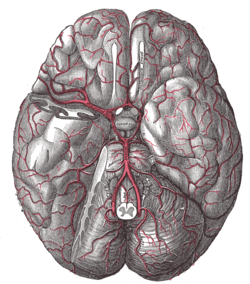

| Artery | superior hypophyseal artery, infundibular artery, prechiasmal artery, inferior hypophyseal artery, capsular artery, artery of the inferior cavernous sinus [1] |

The arteries of the base of the brain.